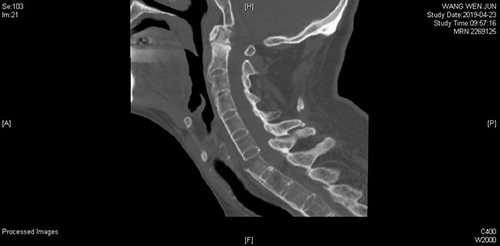

患者王先生,山东淄博市人,不慎摔伤后出现颈部疼痛,四肢放射痛及麻木感,颈部活动受限,四肢功能障碍,摔伤12天后入住山东省立医院脊柱外二科。脊柱外科丰荣杰等详细查看及分析患者的X线、CT、MRI影像学检查认为:患者C6双侧椎板骨折、C6-7椎体骨折脱位并椎管内血肿,C4-C5水平脊髓损伤,C4-T12水平硬膜外血肿,颈部软组织水肿,且患者患有强直性脊柱炎30余年。

手术前后影像学对照(术前C6双侧椎板骨折、C7椎体完全骨折脱位,术后达到解剖复位)

前后路联合手术,使患者颈椎的稳定性大大增加,术后早期就可以下地行走。经过全程监护和系统治疗,患者术后恢复良好,骨折解剖复位,复查X线及CT显示固定位置佳,术后3天即下地行走,术后4天即出院回家休养。